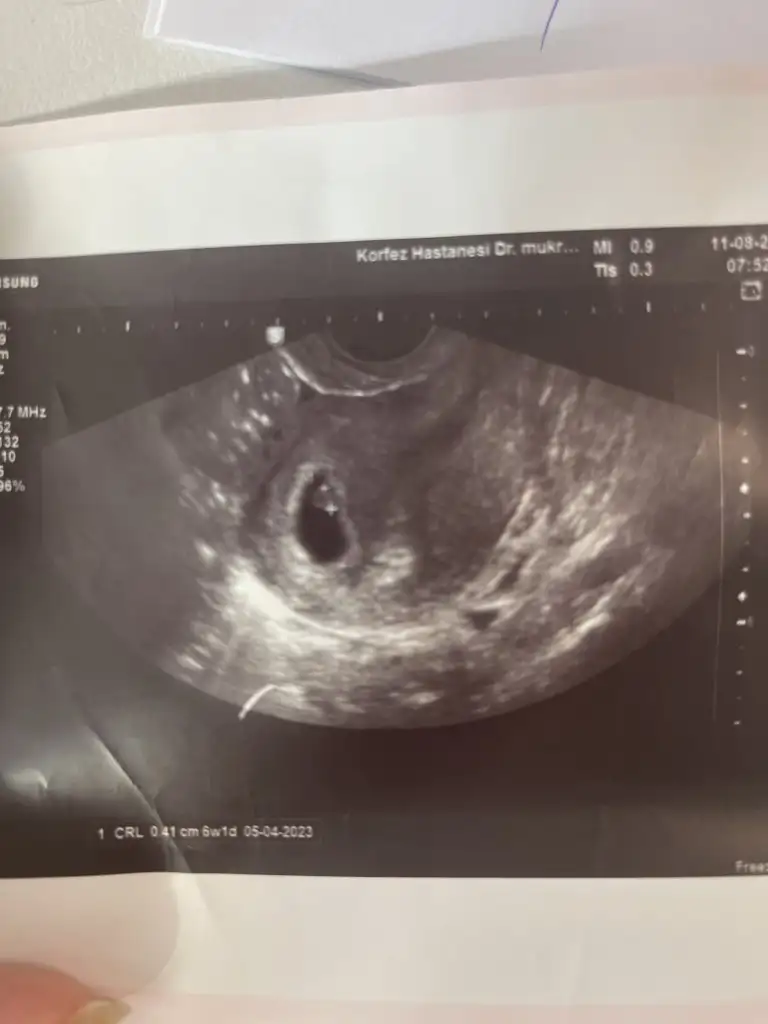

Canım bnde 10 senedir içiyorum 10 ağustos akşamı öğrendim hamile olduğumu hastaneden çıktığım anda bıraktım bir nefes bile çekmedim sonra hiçte canım istemedi öyle söyliyim. benden 9 gün sonrada eşim bıraktı sigarayı1 ayı geçti onunda maşallah hiç istemedik. inşallah sende hemencik iğrenirsin isteğin biter tamamenSelammm,

Ben gecen hafta öğrendim 4 haftalık hamile olduğumu. Öğrendiğim gibi bir anda bıraktım (20 yıldır içiyorum) aşırı zorlanıyorum. Bugun 6. gün ve halen nikotin isteği var. Sizin kaçıncı günde isteğiniz azaldı?